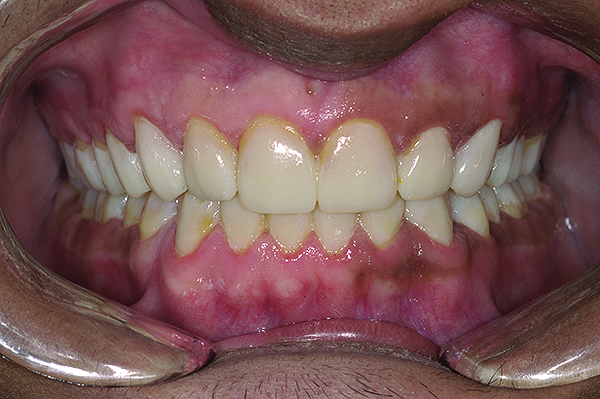

Figure 2. Preoperative 1:2 retracted frontal view.

Figure 2

A thorough clinical examination and analysis were carried out to assess the esthetic and functional problems of the patient (Figure 2 through Figure 7). The medical history was non-contributory, except for mild leukoderma. Temporomandibular joint (TMJ) function was within normal range.

Mounted study casts were used to evaluate occlusion. The relevant findings were as follows2: Facial analysis revealed a canted maxillary occlusal plane and canted dental midline. Dentolabial analysis showed that the maxillary incisors were not adequately visible during repose; it also revealed a reverse smile line, as well as a wide smile showing 12 teeth. Results from the phonetic analysis were that “F” and “V” sounds revealed upper incisal shortening, “M” and “S” pronunciation disclosed a diminished vertical dimension of occlusion (VDO), and “E” sounds showed severe shortening of incisors. Dental analysis revealed thick biotype, asymmetry and inappropriate location of gingival levels and zenith, incorrect axial inclinations, a displeasing width-to-length ratio, and pitted surfaces on most teeth. Interproximal decay was evident on several posterior teeth, as revealed by radiographic analysis. Finally, occlusal examination indicated discrepancy between maximum intercuspation (MIP) and centric relation (CR) as well as a lack of anterior guidance/posterior disclusion.